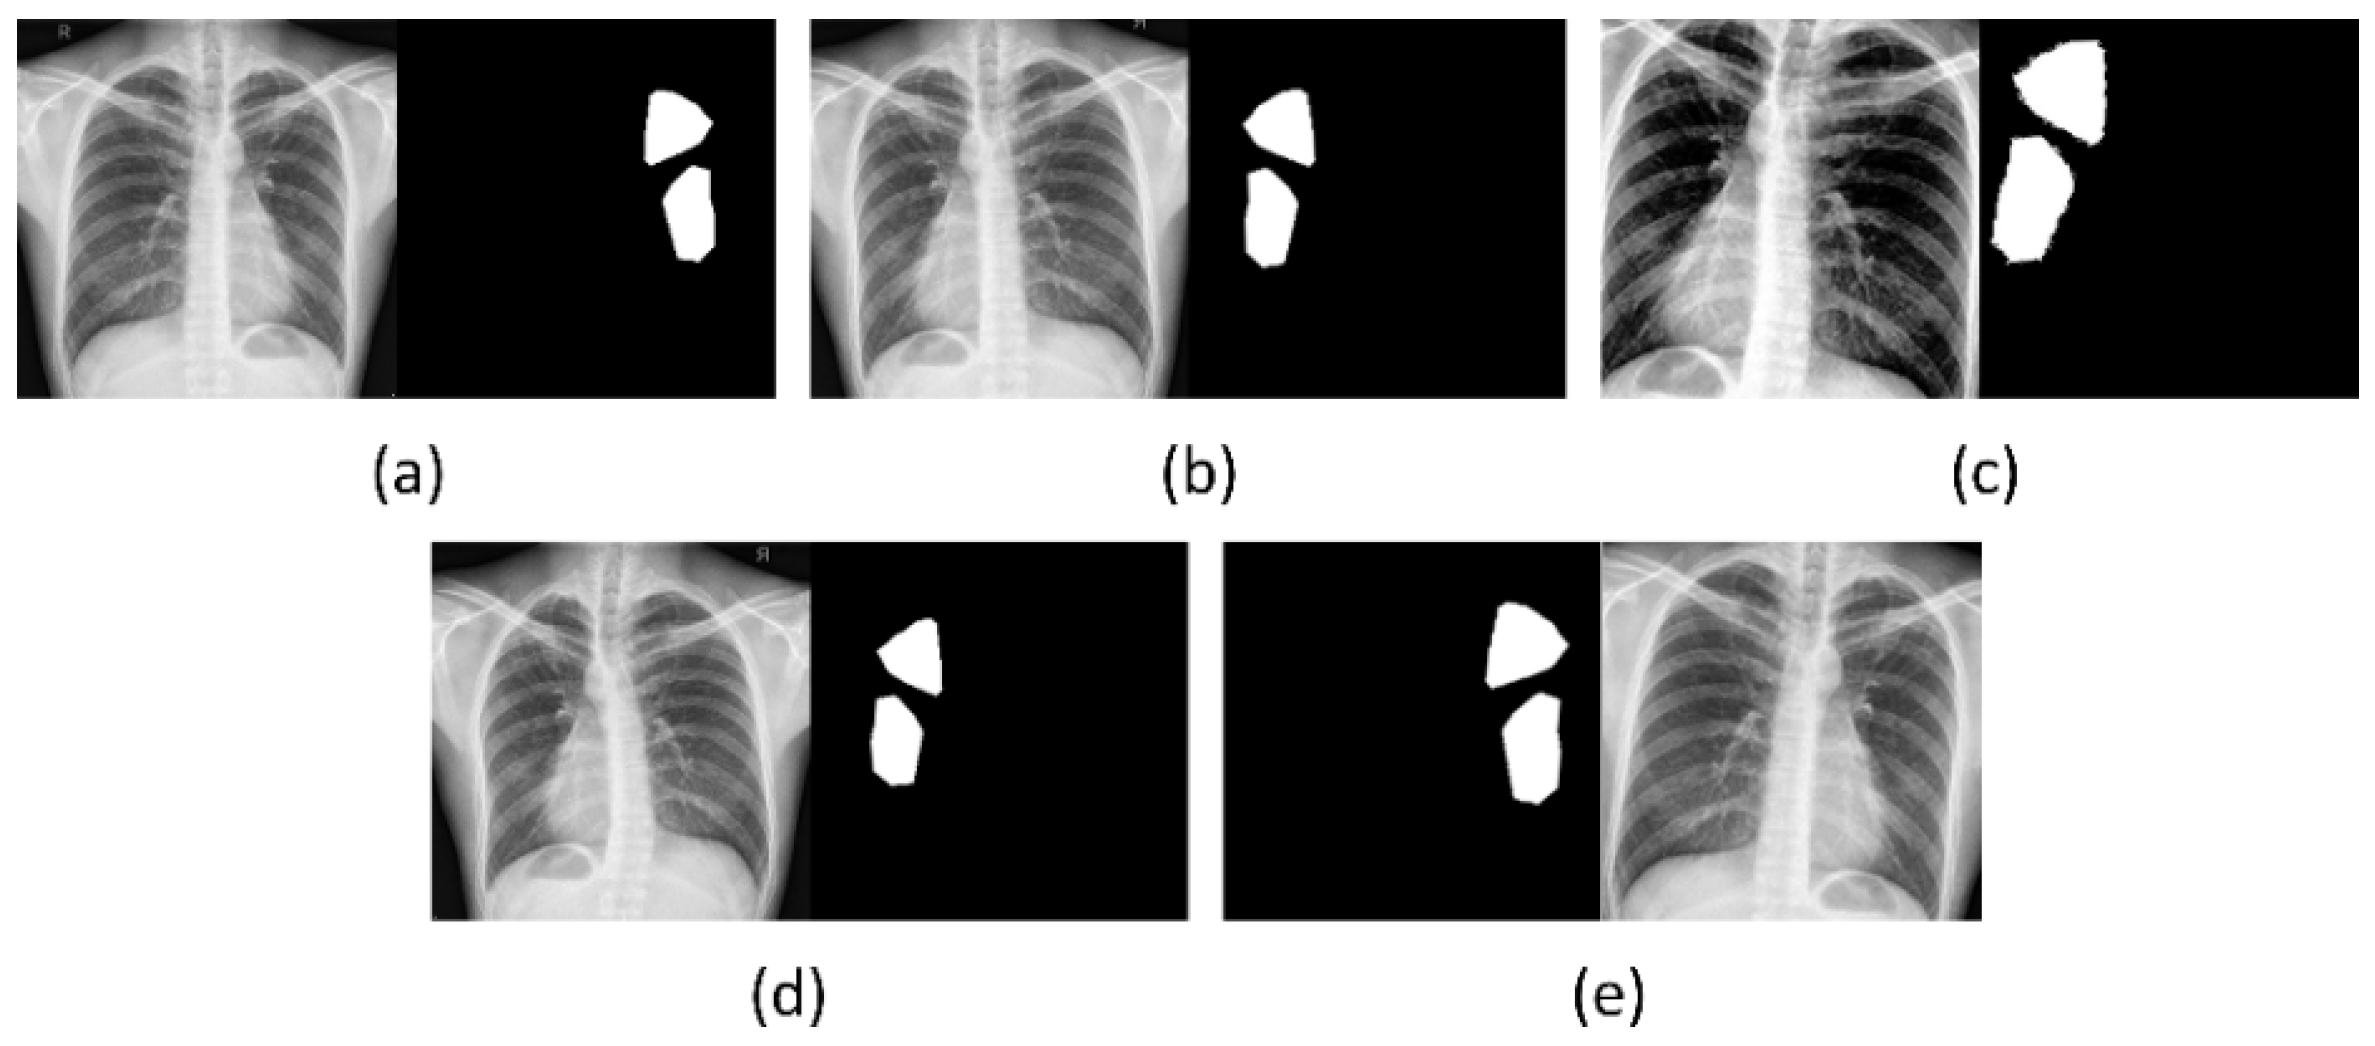

2.1. Data Collection and Preprocessing

2.3. TB-Consistent Region Segmentation